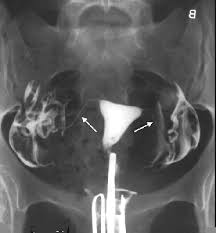

ماذا تعرفين عن اشعة الصبغة للرحم وأهميتها مستشفيات مغربي

تصوير الرحم وقناة فالوب بأشعة الصبغة أو الاشعة الملونة الطبي